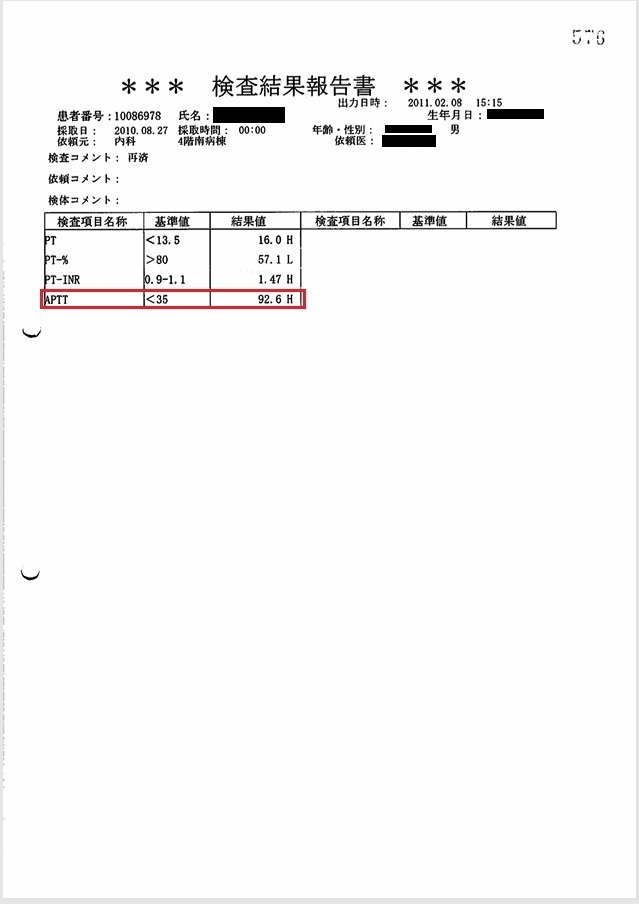

- 8月27日:APTT 92秒でヘパリン増量(死期を故意に早めようとした疑い)

胸腔、心嚢内への出血によるショックの進行中、8月27日の血液検査でAPTT 92秒とパニック値にもかかわらず、ヘパリンを15000単位から20000単位に増量。故意に死期を早めようとした疑い。

証拠:血液検査・注射処方箋の抜粋(赤枠部分)

8月27日の午後3時の時点で、血圧60/40 mmHg, 心拍数150~160/min、8時間尿量4mlと、いつ心肺停止してもおかしくない状態であった。 しかし医師は父がショックに陥った原因を「元々の心筋梗塞が重症のため」と偽り、 医療事故とそれに起因する緊張性血胸・心タンポナーデ、出血性ショックを隠蔽した。 またヘパリン15000単位/日が投与されていたが、この日の血液検査でAPTT 92秒とヘパリン投与量が過剰であったにもかかわらず、ヘパリンが20000単位/日に増量されており、故意に死期を早めようとした疑いがある。